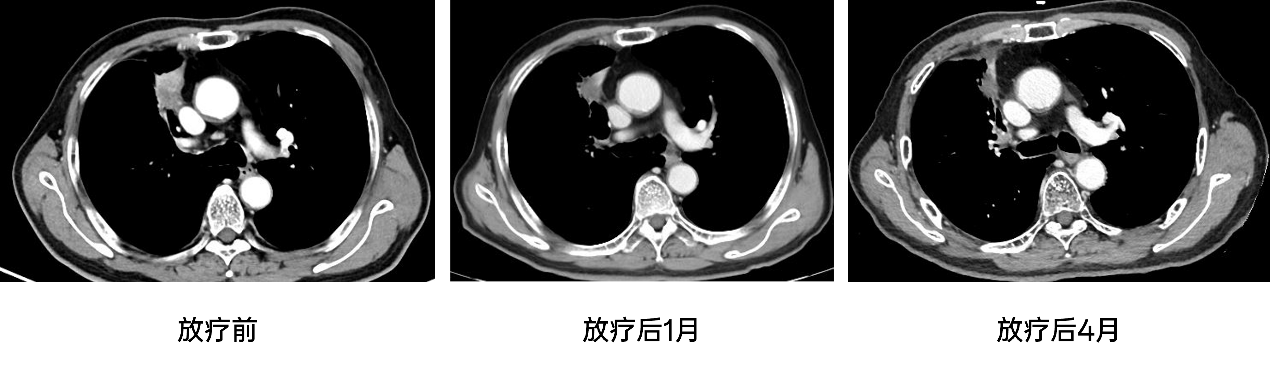

疗效评估:2024-06-25,放疗后1月复查CT:1、"右肺癌"治疗后,右上肺前段仍可见肿瘤性病变,较前缩小;纵隔4、7组淋巴结肿;2、两肺肺气肿;两上肺结节钙化并条索状影,右中肺及右侧胸膜钙化灶,考虑陈旧性结核,均较前无明显变化;3、右肾囊肿,较前缩小;4、腹主动脉壁间血肿形成可能,主动脉就髂动脉粥样硬化,较前无明显变化。

2024-11-26,放疗后4月复查CT:1、"右肺癌"治疗后,右上肺前段仍可见肿瘤性病变,较前缩小,周围间质性炎症;纵隔4、7组淋巴结肿同前;2、两肺肺气肿;两上肺结节钙化并条索状影,右中肺及右侧胸膜钙化灶,考虑陈旧性结核,均较前无明显变化;3、右肾囊肿,较前缩小;4、腹主动脉壁间血肿形成可能,主动脉就髂动脉粥样硬化,较前无明显变化。